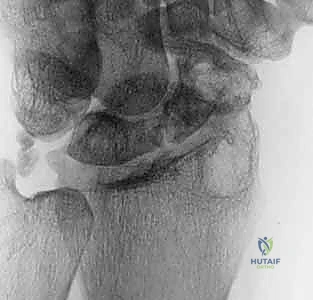

5. تحضير العظم الزورقي (Debridement)

يتم فتح كبسولة مفصل الرسغ للوصول إلى العظم الزورقي المكسور. يقوم الدكتور هطيف بتنظيف منطقة عدم الالتحام بالكامل، وإزالة كل الأنسجة الليفية، والتكيسات، والعظام الميتة (النخرية) باستخدام أدوات دقيقة (Curettes) ومثاقب صغيرة، حتى يصل إلى حواف عظمية صحية تنزف دماً (علامة على الحيوية). هذا يترك فجوة بحاجة إلى الحشو.

![تحضير وتجهيز العظم الزورقي لاستقبال الطعم](/media/hutaif_opertive/hutaif-ch